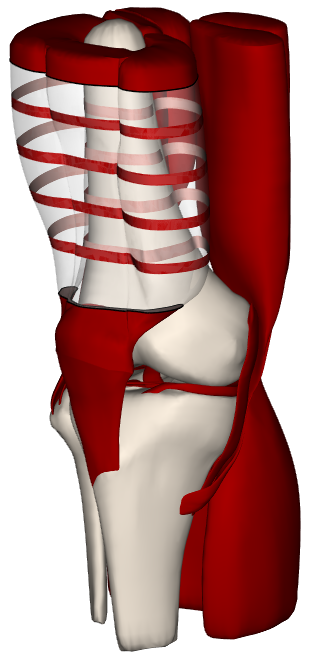

RibbonView: Interactive Context-Preserving Cutaways of Anatomical Surface Meshes, T. McInerney and P. Crawford, 6th International Symposium on Visual Computing (ISVC 2010), Las Vegas, NV, Nov. 2010. |